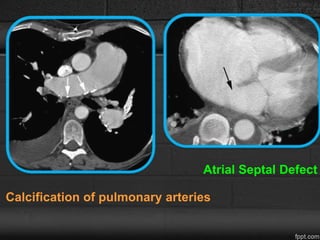

• Calcification of the pulmonary arteries, usually affecting

the main, right, or left pulmonary arteries - Irreversible

vascular disease.

CT

Calcification & thrombus

Abnormal vascular connections such as ASD, partial

anomalous pulmonary venous return & PDA.

Calcification of pulmonary arteries

Atrial Septal Defect

Calcification of pulmonaryarteries Atrial Septal Defect